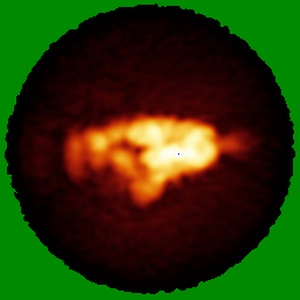

Negative stain EM map of SARS-CoV-2 Spike in complex with CoVIC-362

Single-particle17.0 Å